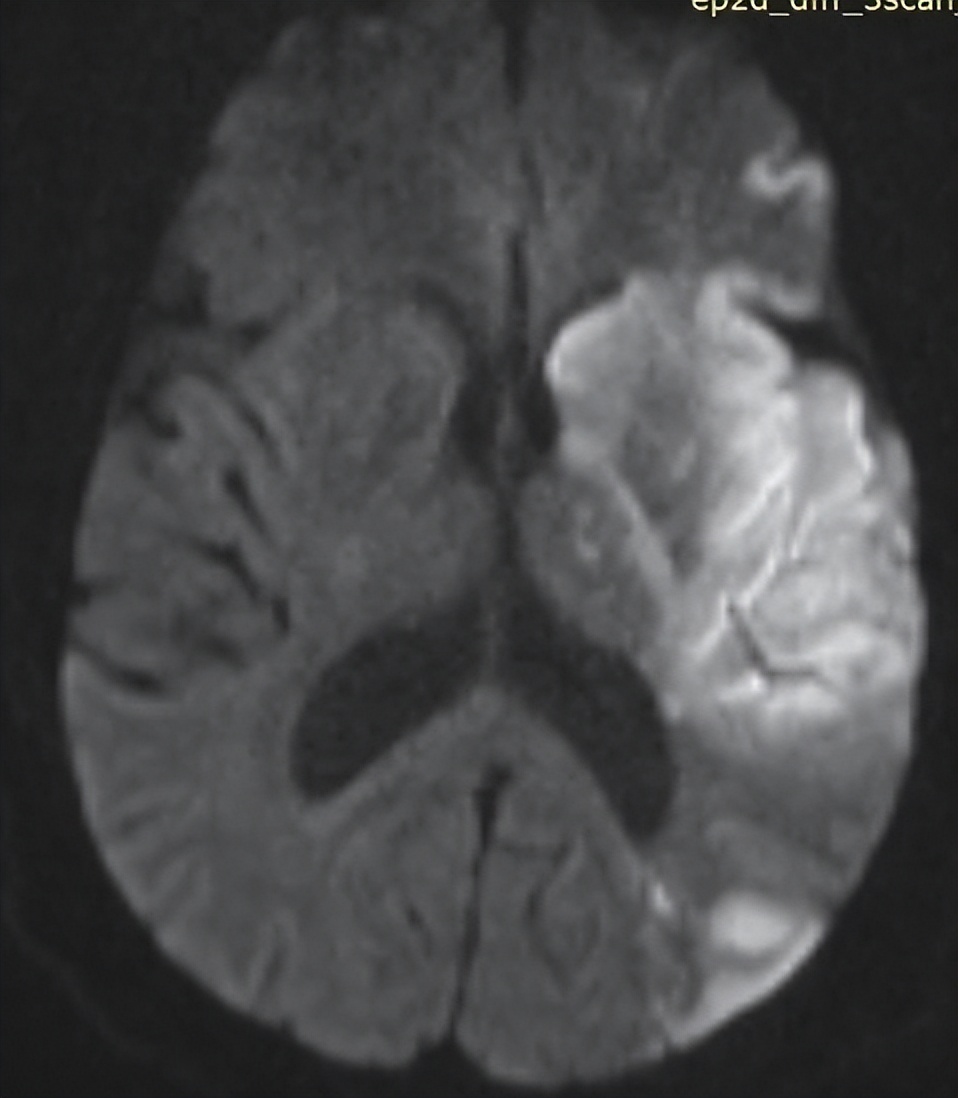

通过查体判断很可能是脑梗,赶紧做了头颅磁共振,确诊就是“急性大面积脑梗”,病灶很大一片。

患者送来还算及时,发病只有1个小时,与家属沟通后,给予静脉溶栓治疗,这项治疗是指南推荐的(静脉溶栓对发病时间要求很严格,发病<4.5小时,错过这个时间就做不了)。

溶栓后,患者右侧手脚有少许活动了,可以在床面小范围来回移动。但是梗死的面积太大了,估计还是会遗留明显的肢体瘫痪。